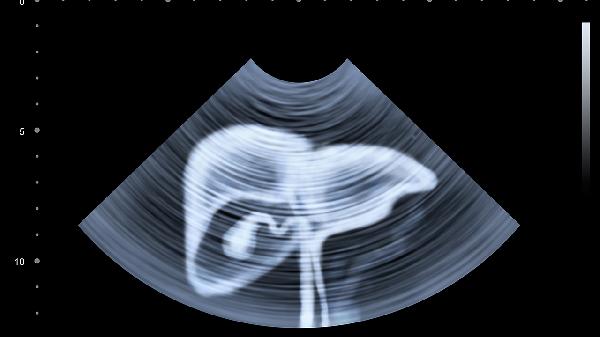

女性左侧卵巢囊肿或子宫肌瘤可能表现为下腹包块,伴随月经异常或排尿不适。超声检查可明确诊断,较小囊肿可观察,较大肌瘤需考虑米非司酮片药物治疗或肌瘤剔除术。